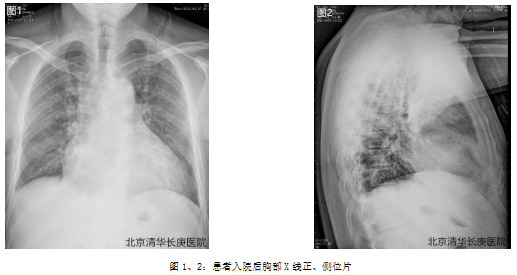

1. 胸部X线正、侧位片:

d.胸片示双肺纹理增粗,心胸比0.68;